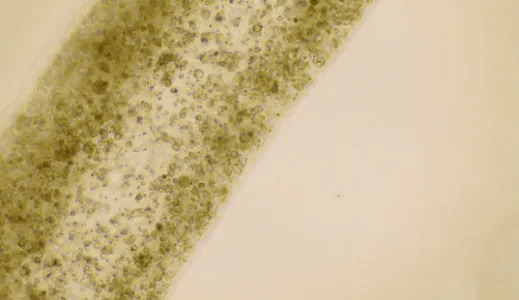

他们的想法相当大胆——通过对一名无精症患者的睾丸进行活检,收集其干细胞进行体外扩增,然后通过3D生物打印成类似于生精小管的管状结构,这些细胞后续成长为参与精子生成的几种特殊细胞,并在精子干细胞维持方面也有着显著改善—这两者都是具有精子生成能力的早期迹象。

△3D打印小管的显微图像